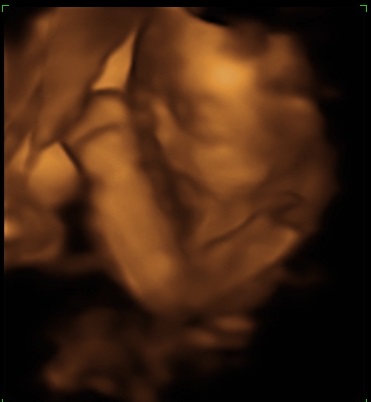

Os dejo las fotos de la semana 23 y 26 de trillizos (solo sale uno porque los otros dos se pusieron de espaldas, que le vamos a hacer, han salido al padre...)

Como podréis observar este pobre tiene el pie del hermano en la boca, y las costillas...y los bracitos tocandole la cabeza..